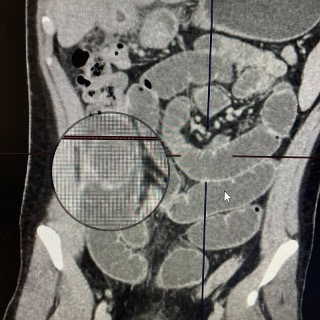

При первичном обследовании стандартные причины кишечной непроходимости были исключены. Для верификации диагноза была экстренно выполнена компьютерная томография органов брюшной полости. Результаты КТ выявили редчайшую причину обструкции: в просвете тонкой кишки был обнаружен крупный конкремент (25-30 мм), полностью обтурирующий просвет кишечника.

Из данных анамнеза известно, что за шесть месяцев до настоящей госпитализации у пациента был диагностирован острый калькулезный холецистит. При УЗИ-обследовании были выявлены два крупных конкремента в желчном пузыре. После купирования воспаления была рекомендована плановая холецистэктомия, которую пациент отказался выполнять. Проведенное обследование позволило установить, что на фоне хронического воспаления сформировалось пузырно-тонкокишечное соустье (холецисто-дуоденальный свищ), через которое конкременты мигрировали в просвет тонкой кишки, вызвав развитие механической кишечной непроходимости — желчного илеуса. В экстренном порядке была выполнена диагностическая лапароскопия.

Компьютерная томография пациента Извлеченные камни